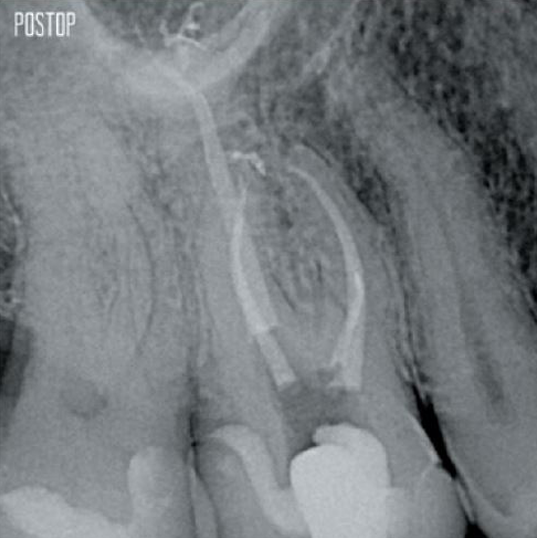

Fotos cortesía del Dr. Ahmed Salman

Más conservación de dentina. Se garantiza la conformación, irrigación y obturación adecuadas.

TruNatomy® conserva la mayor cantidad de dentina posible1 y ofrece una solución completa que incluye irrigación y obturación coincidentes.

La unión de la geometría de la lima, la conicidad regresiva y el alambre delgado y altamente flexible permite un tratamiento eficiente del conducto radicular y, al mismo tiempo, elimina solo la dentina cuando es clínicamente necesario.1